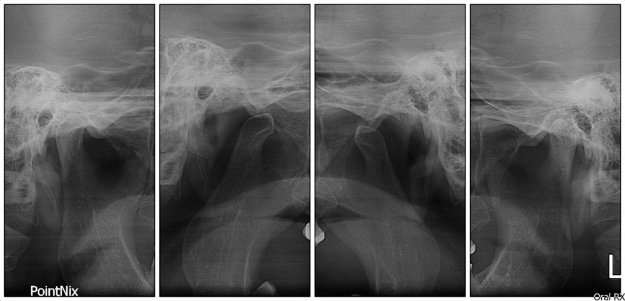

ATM

Técnica radiológica  que proporciona información sobre la Articulación Temporo –Mandibular.

Podemos observar forma de las cabezas condilares y estado de las superficies articulares desde un punto de vista lateral y la amplitud del movimiento de los cóndilos con boca abierta.